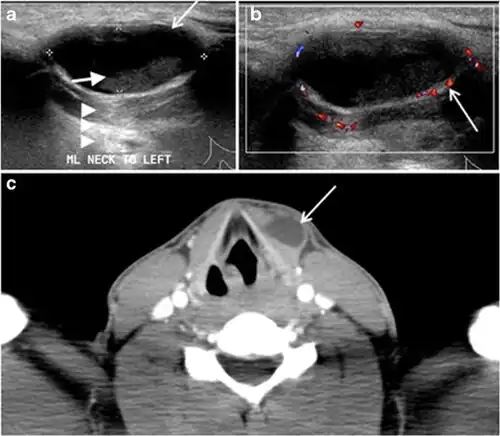

Fig. 7. A 51-year-old female patient post total thyroidectomy for PTC with elevated thyroglobulin measurement. an Axial non-enhanced CT scan of the neck at the level of the thyroid bed demonstrates a well-defined, rounded, homogenously dense soft tissue situated between the trachea and left internal jugular vein (white arrow). b Transverse ultrasound image of the neck demonstrates a well-defined, homogeneous, hypoechoic soft tissue nodule measuring 6 mm (white arrow) with no detected micro-calcifications. Biopsy showed a predominantly residual normal thyroid tissue with micro-foci of PTC.[1] -